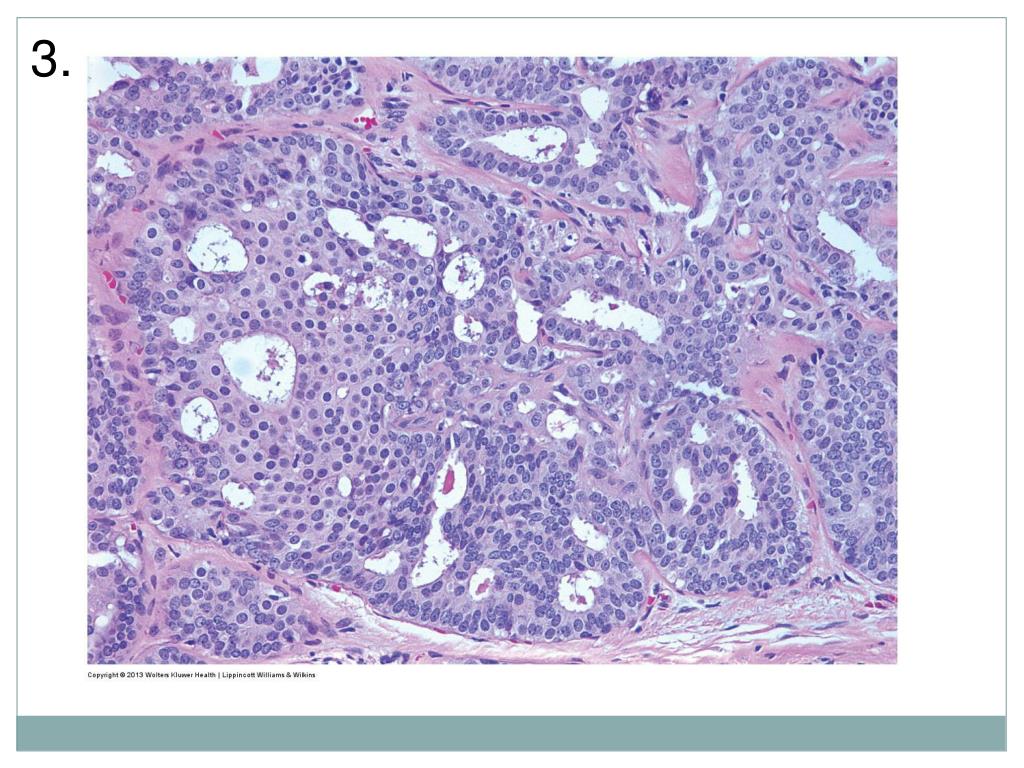

Bottom Line

6. 4.

9. Answers Pre-quiz Post-quiz 1. UDH 2. ADH 3. DCIS 4. FEA 5. UDH 1. UDH 2. ADH 3. ADH 4. UDH 5. FEA 6. CCC